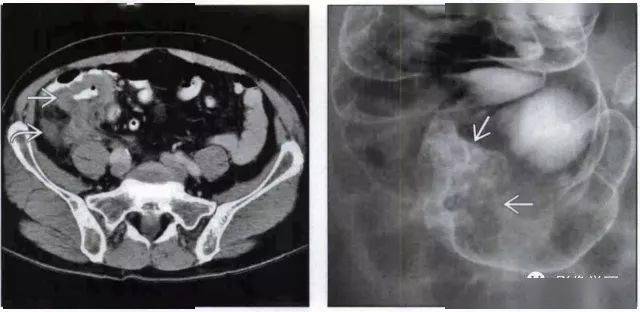

回盲部占位或炎症的影像鉴别诊断